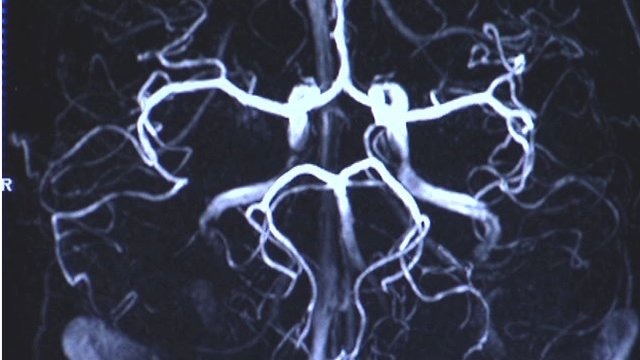

Cuando las campañas de Kickstarter terminaron unas semanas más tarde, 18 de los proyectos habían ganado fondos suficientes para seguir adelante. Examinando las exploraciones cerebrales de los participantes, el equipo descubrió que la actividad en una región llamada el núcleo accumbens había sido diferente cuando se consideraron proyectos que posteriormente pasaron a tener éxito.

Esto puede ser debido a que hay que sopesar varios factores para tomar decisiones. Por ejemplo, su actividad de nucleus accumbens, que está asociada con esperar una recompensa, podría aumentar con la perspectiva de comprar una galleta de chocolate, pero otras regiones de su cerebro pueden estar en desacuerdo, diciéndote que se supone que tienes que estar a dieta.

Incluso si no compras la galleta, dice Knutson, el núcleo accumbens podría prevalecer en otras personas, o conducir a comprar la galleta en una fecha posterior. «Si podemos desconstruir el proceso de toma de decisiones en el cerebro, entonces podemos identificar la actividad que representa la intención de lo que una persona, en promedio, hará finalmente», afirma Knutson.